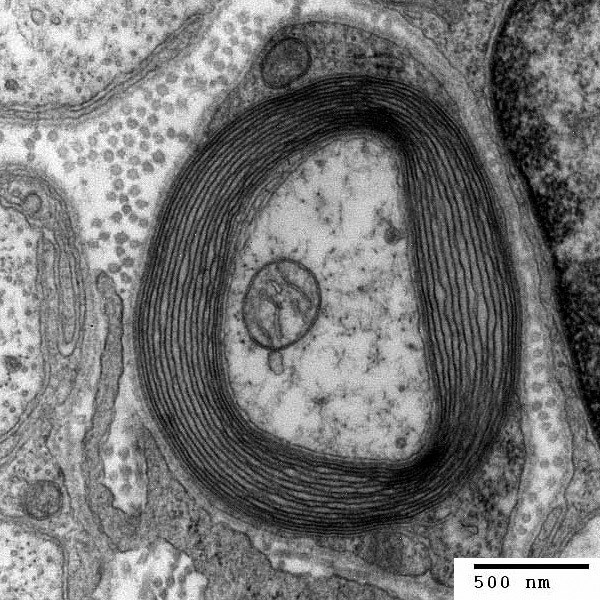

Myelinet beskrivs ofta som ett "fetthölje", men det är faktiskt ett utskott från en annan cell. Nervcellens axon omsluts av ett utskott från en annan typ av cell (glialceller i centrala nervsystemet, och Schwanceller i perifera nervsystemet). Bilden nedan visar ett tvärsnitt av en nervcells axon. Och i bilden ses de lager på lager av myelinutskott från en glialcell, med utskottet rullat/lindat runt axonen i massvis med lager (motsvarande "4" i illustrationen).

1. Axonen

2. Nucleus of Schwann cell (det är cellen som skapat utskotten kring axonen)

3. Schwann cell

4. Myelin sheath (dessa lager av myelin är det som oftast bara kallas myelin)

5. Neurilemma